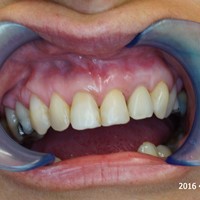

Wskazania do wykonania resekcji zębów 21, 22. Prawie niewidoczna blizna pooperacyjna.